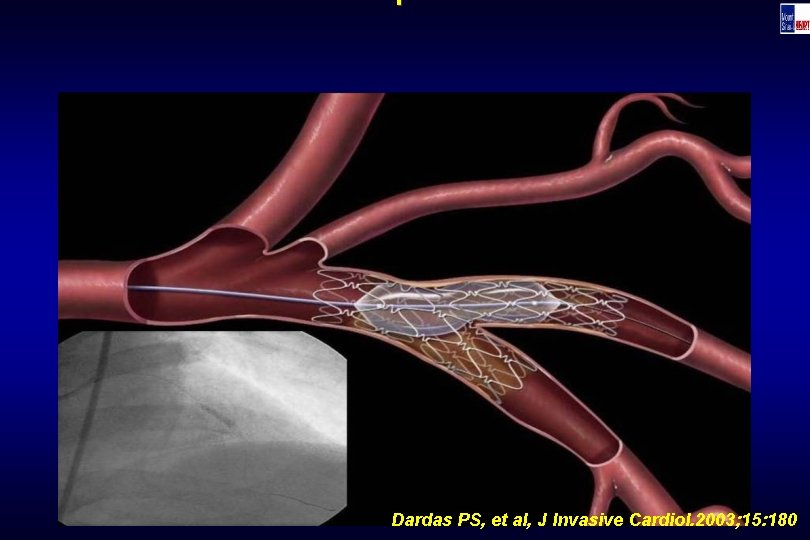

Technique Dardas PS, et al, J Invasive Cardiol. 2003; 15: 180

Technique Dardas PS, et al, J Invasive Cardiol. 2003; 15: 180

Technique Dardas PS, et al, J Invasive Cardiol. 2003; 15: 180

Technique Dardas PS, et al, J Invasive Cardiol. 2003; 15: 180

Technique Dardas PS, et al, J Invasive Cardiol. 2003; 15: 180

Technique Dardas PS, et al, J Invasive Cardiol. 2003; 15: 180